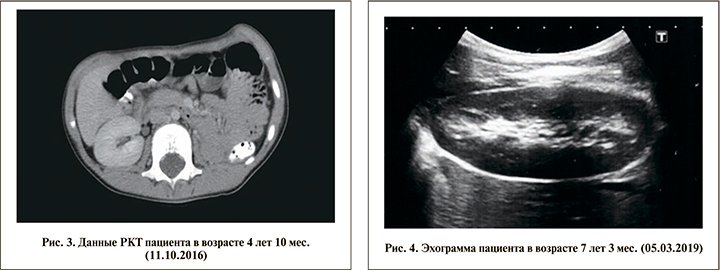

Ежегодно ребенок проходит диспансерное наблюдение в Республиканском центре детской урологии-андрологии на базе ГАУЗ ДРКБ МЗ РТ (рис. 3). По состоянию на март 2019 г. по результатам контрольного обследования (УЗИ) патологии брюшной полости не выявлено, отмечается викарная гипертрофия оставшейся части правой почки (рис. 4). Наружные половые органы сформированы по мужскому типу: половой член возрастных размеров, меатус открывается на головке полового члена, мочеиспускание свободное и безболезненное; гонады расположены в мошонке, размеры левого яичка соответствуют возрастным показателям, правое яичко гипоплазировано. Состояние мочевыделительной системы по данным биохимического анализа крови, анализов мочи оценено как удовлетворительное. Как и ранее, данных за протеинурию нет. Содержание мочевины и креатинина в пределах нормы.